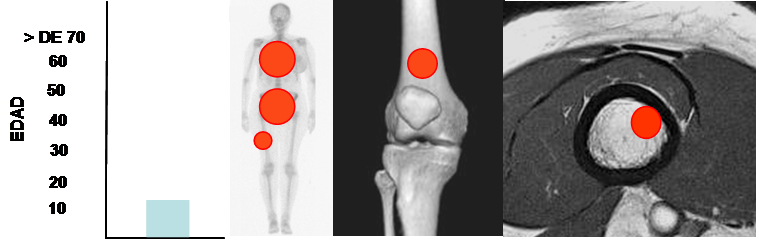

Pueden presentarse a cualquier edad y la mayoría se encuentran en la 1º década.

Se localizan en la medular del hueso, con frecuencia en la pelvis, costillas y fémur. (16). (Fig 50).

Muestra poca o ninguna actividad en la gamagrafía, que sirve para diferenciarlo de lesiones osteoblásticas. (13).

Fig 50. Enostosis.

Mayor frecuencia en la 1º década. Predominio en pelvis, fémur y costillas.

Lesión diafisiaria, de ubicación excéntrica.